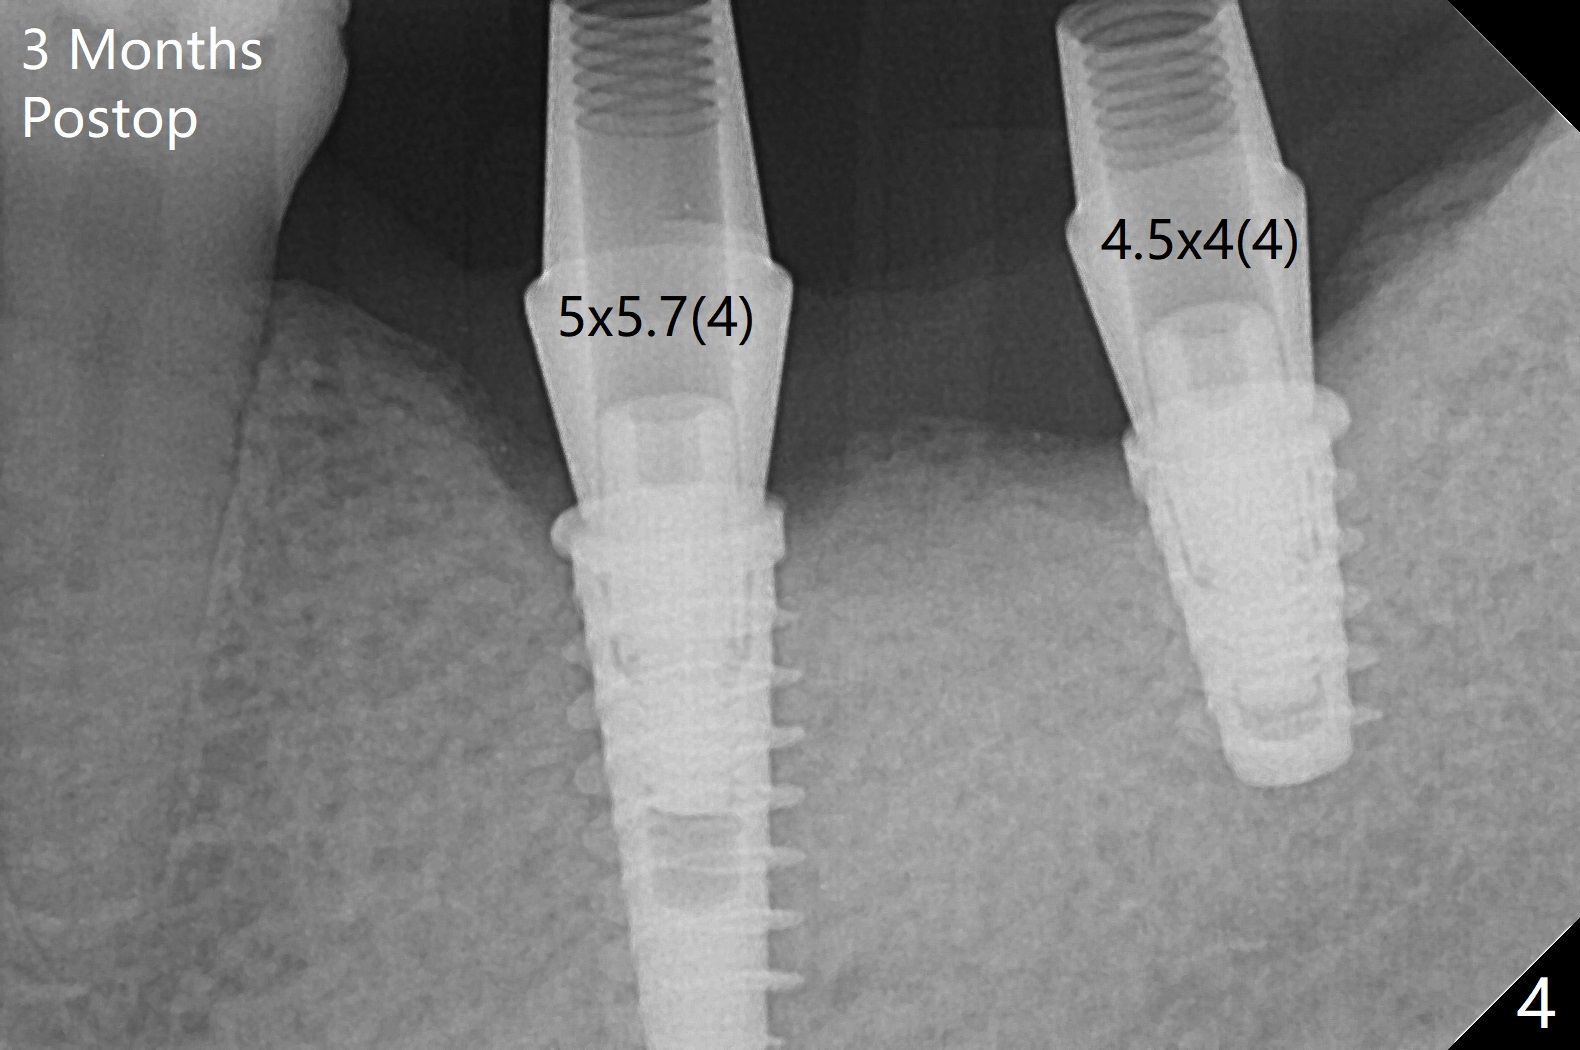

Following placement of a 4.5x11 mm implant at #19 (14 months post guide fabrication), a fixture anchor pin is placed. With stable guide, it is much easier to finish osteotomy and implant placement at #18 (Fig.1). Since the patient is nervous and sensitive to drilling, a shorter implant is placed (7 mm instead of 9 mm vs. 8.5 mm drill). The stability is unaffected because of the dense bone. After use of 5.5 mm profile drill, healing abutments (5.5x3 and 5.5x4 mm) are placed without interference. There is crestal bone loss in 3 months (Fig.2, as compared to Fig.1). Since there is more space apical to the pair abutment at #19 than that at #18, incomplete abutment seating is suspected at #19. More X-ray will be taken (Fig.3,4). In fact, it is not necessary. The space differential is also noted with healing abutments in Fig.1. BW cannot tell whether the abutment at #19 is seated or not (Fig.3). When the abutment is changed at #19 with 30 Ncm torque, the space differential remains (Fig.4, as compared Fig.2) and must be normal. The shorter implant at #18 appears not osteointegrate, since the patient feels pain when the abutment is torqued at 15 Ncm. The patient returns for temporary crown contour adjustment 1-2 weeks later. The implant at #18 is removed when the abutment screw is untightened 7 months postop; Cortical bone is placed with 6 month membrane (Fig.5). Three months later, incision will be made with reuse of the guide with fixture pin at #19. If a 4.5x9 mm implant cannot be placed, bury a short and/or narrow implant. Impression will be taken for #19 soon. In fact fixture pin cannot be seated. It appears that cancellous bone reforms, presumably low density. Underdrilling is conducted in diameter. The torque is high, but normal drilling is not carried out. The former implant exfoliated probably due to compression necrosis. The new implant is not completely seated, partially out of fear of being close to the Inferior Alveolar Canal (Fig.6). After cortical plate perforation, allograft is placed (Fig.7 *), followed by buccal flap release (periosteum underscored). In fact the implant does not have enough clearance from the Canal (red dashed line: the superior border of the Canal). The abutment at #19 returns to hold periodontal dressing in place. The implant is buried in the bone except lingual 4 months postop (Fig.8,9).